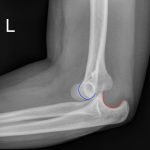

Elbow dislocations are classified by the position of the radio-ulnar joint relative to the humerus.1 Images 1, 2, and 3 show a left posterior elbow dislocation; the radius and ulna are displaced posteriorly with respect to the distal humerus. The lateral view of the elbow most clearly shows this: trochlear notch of the ulna is empty and displaced posteriorly relative to the trochlea. There is no associated fracture. Images 4 and 5 show the elbow status-post reduction, demonstrating proper alignment of the distal humerus with the radius and ulna.